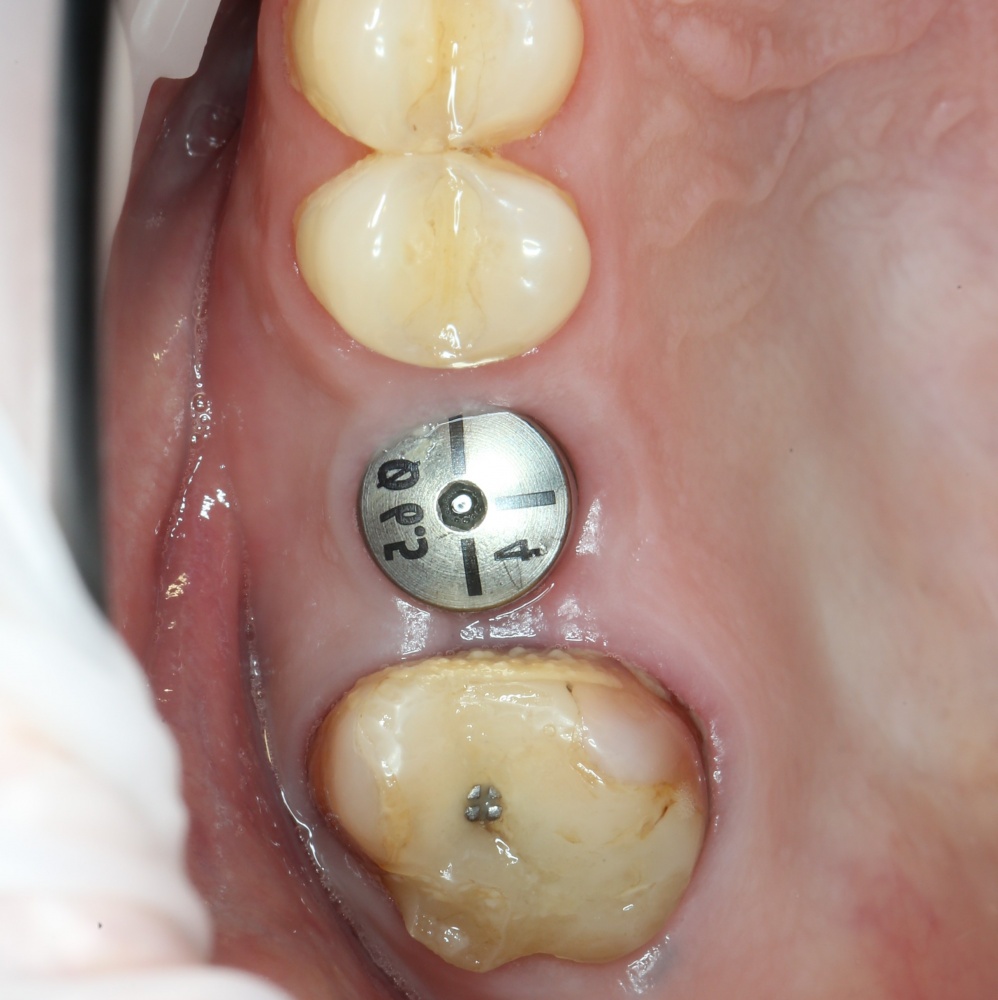

Через неделю можно снять швы. Область раны выглядит следующим образом:

А через два месяца — вот так:

На этом этапе, для создания более правильного десневого контура, можно поменять формирователь размер больше:

А еще через месяц — поставить временную коронку: